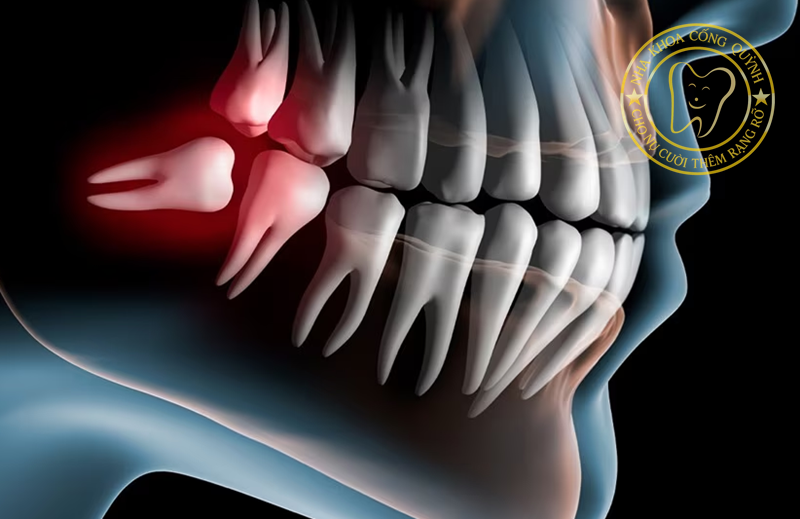

Răng khôn (răng số 8) thường mọc ở độ tuổi 17–25, khi xương hàm đã ổn định. Do không còn đủ khoảng trống, răng khôn dễ mọc lệch, mọc kẹt hoặc ngầm sâu dưới nướu, gây ra nhiều biến chứng ảnh hưởng sức khỏe răng miệng.

Bạn nên nhổ răng khôn trong những trường hợp sau:

Giảm đau và ngừa viêm lợi trùm

Tránh sâu răng số 7 và hư tủy

Ngừa xô lệch hàm sau khi niềng

Tránh biến chứng u nang, áp xe răng khôn

Bảo vệ sức khỏe răng miệng lâu dài